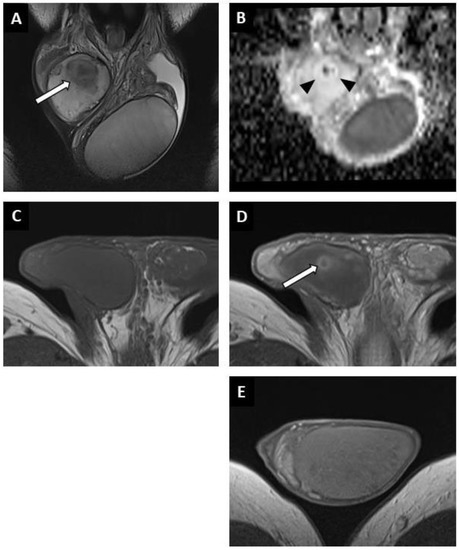

Figure 4. Partially regressed seminoma of the right testis in a 52-year-old man (symptomatic metastatic retroperitoneal nodes). Coronal T2W image showing a nodule with ill-delineated margins in hyposignal (white arrow) (A). Coronal reconstruction of an ADC map showing a focal elevation of ADC values (black arrowheads) with a central area of restriction (in black) (B). Before injection, no focal abnormality was visible on the axial T1W sequence (C). After intravenous injection of the contrast agent, a large area of reduced enhancement was visible (overlapping the lesions compared to the T2W images) with a central enhanced nodule (white arrow) (D). Axial post-injection T1W image of the left testis showing the usual testicular parenchymal enhancement (E). Pathological analysis revealed a 5 mm residual seminoma within a 2 cm fibro-hyaline patch.

BOTTs appeared as round or oval nodules (81%) (Figure 3 and Figure 4) or a focal area with irregular boundaries (19%) on the T2 sequences (hyposignal). No lesions were visible on the T1 sequences (isosignal) (Figure 4C).

The diffusion-weighted sequences showed nodular areas of reduced signal with increased ADC values (mean value: 2 ± 0.3 × 10−3 mm2/s) (Figure 2E and Figure 3F) compared to contralateral parenchyma (mean value: 1.3 ± 0.3 × 10−3 mm2/s) in all patients (significant difference, p < 0.01). The mean ADC ratio was 1.6 ± 0.3. Within these areas with increased ADC values, a restrictive nodule (Figure 4B) was detected in six of the seven patients that were diagnosed with a partially regressed testicular tumour.

Dynamic contrast-enhanced sequences showed areas of reduced enhancement in all cases. The size of this area matched that of the lesion on the T2 sequences (Figure 3G) in 11 patients (26.2%), and in 31 patients (73.8%) it overlapped the lesion with reduced enhancement extending to the peripheral parenchyma (Figure 2F and Figure 4D). In the cases of partial tumour regression, dynamic contrast-enhanced sequences revealed early and strongly enhanced focal abnormalities within areas of reduced enhancement, corresponding to nodules in six patients (Figure 4D), and an ill-delineated area with increased enhancement in one (corresponding to the patient in whom no focal abnormality that was suggestive of a viable tumour was found upon US examination).

A lymphoplasmacytic infiltrate in the fibrous tissue was reported in 28 cases (58%), was absent in one and was not specified in the others. In all cases there were completely hyalinized tubules that were mainly associated with a “Sertoli cell only” pattern peripheral to the scar. Impaired spermatogenesis was seen in all the patients. Intratubular germ-cell neoplasia (IGCN) was found in nine patients (18.8%) peripheral to the area of scarring, which was associated with partial tumour regression in four cases. In the six cases of partial tumour regression, the lesions found were pure seminomas.